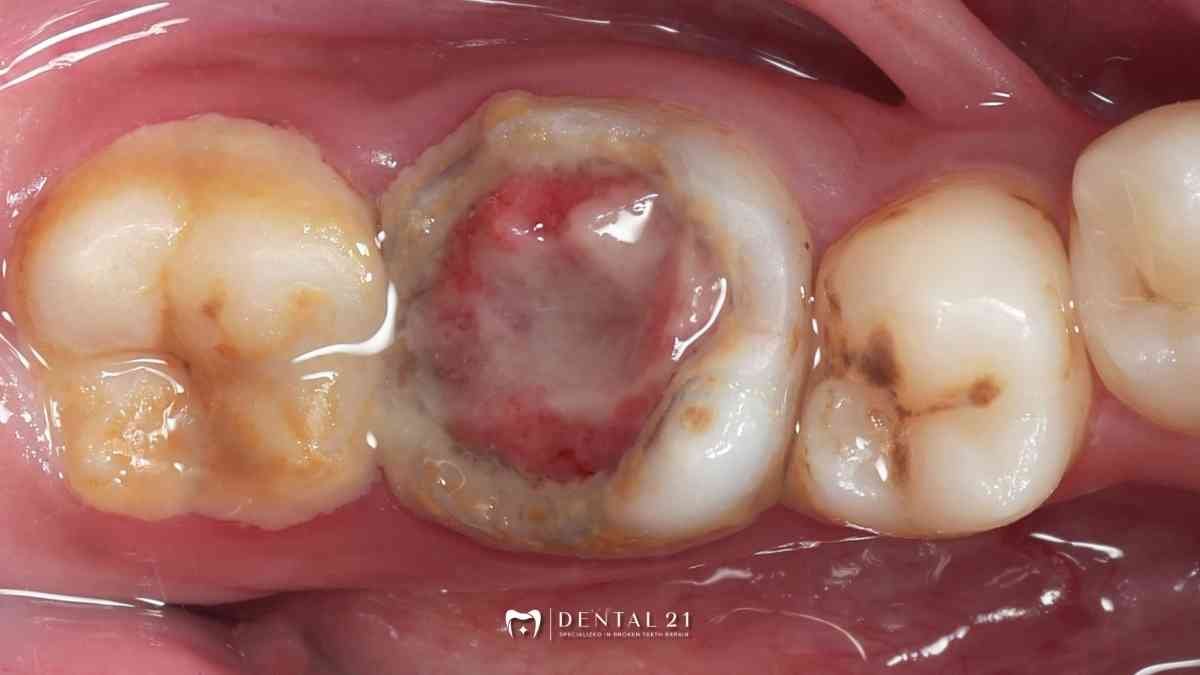

Istilah “daging keluar dari gigi” bukan istilah medis. Umumnya, yang terlihat adalah jaringan lunak berwarna merah/pink yang muncul:

- dari lubang gigi yang besar, atau

- dari gusi di sekitar gigi bermasalah.

Pada kasus gigi berlubang besar, jaringan itu sering muncul karena iritasi yang berlangsung lama pada bagian dalam gigi. Karena itulah, keluhan biasanya tidak hanya “mengganjal”, tapi juga nyeri saat dipakai makan.

- kadang timbul jaringan yang tampak seperti “daging” di dalam lubang